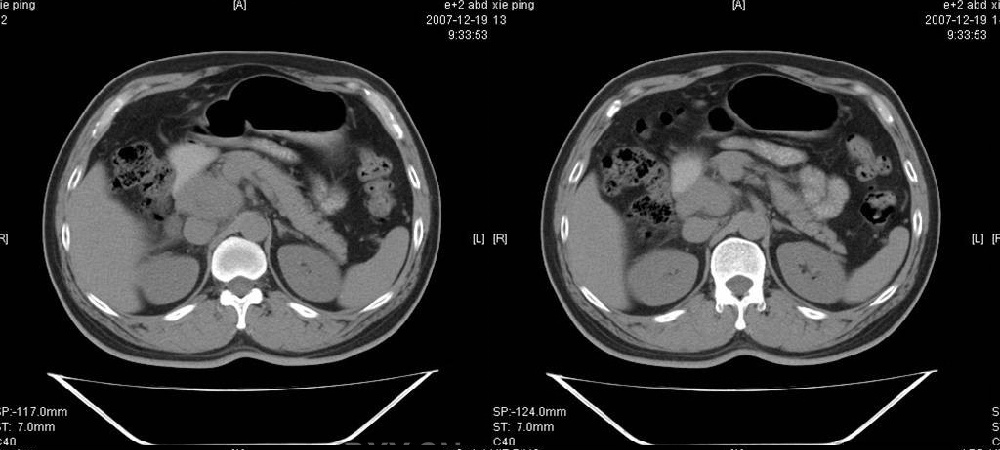

临床病史:患者,男,53岁,因反复上腹部饱胀不适2+月,在餐后或饥饿时明显,伴呃逆,无呕吐、呕血,无腹痛腹泻;2年前腹腔镜胆囊切除,否认肝炎、结核等病史。

体格检查:一般情况可,腹平软,全腹无压痛,无反跳痛,未扪及包块,肝脾未及,肠鸣音正常。白细胞6.03×10e9/l,中性粒细胞3.32×10e9/l,淋巴细胞2.06×10e9/l

胰腺头部低密度囊性病灶,边缘清楚,增强后囊壁略强化。考虑:胰头假性囊肿!

胰腺头部(或肝脏尾叶部)低密度囊性病灶,边缘清楚,增强后囊壁略强化。考虑:胰头假性囊肿. 或肝脏尾叶部囊肿。

考虑十二指肠憩室。从影像上看,病变位于下腔静脉前胰头后方十二指肠内侧,肝尾叶受压,说明病变来源于后腹膜;胰胆管成像胰管和胆道未见扩张,总胆管中段受压未显示,上下段正常,所以不考虑来源与于肝尾叶和总胆管的囊肿。考虑为十二指肠憩室或小网膜囊肿。

楼上高手,本例的确是一例十二指肠憩室.